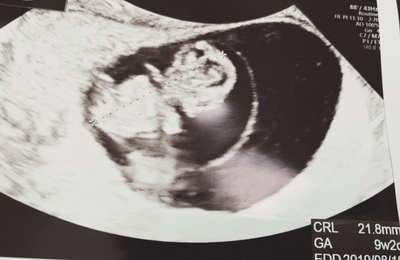

明けましておめでとうございます。 年末年始は私の実家で過ごしました。去年も私の実家で過ごしたので年明けに旦那の実家に行こうと思ったのですが、私の体調が悪くなり行けませんでした・・。 お義母さんにはまだ妊娠の事は言ってません。旦那からは「安定期に入ってからで良い」と言われましたが、次直接会った時に言おうと思っていたので、お正月会いに行けなかったのは悔やまれます・・。 今回の帰省はつわりも落ち着いてい…